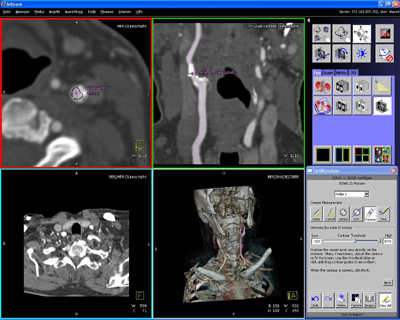

A Siemens Orvostechnika (Medical Solutions, Med) ágazata új funkciókkal illetve alkalmazásokkal bővítette komputer-tomográfiai kliens-kiszolgáló megoldását. A syngo WebSpace segítségével CT felvételeket lehet interneten vagy más hálózati kapcsolaton keresztül felhívni és azokat elemezni, kezelni. A csomag egyik új alkalmazásának neve syngo InSpace AVA (Advanced Vessel Analysis). Ez új algoritmusok és eszközök segítségével lehetővé teszi apró vagy kevéssé kontrasztos erek és úgyneveuett szubtotális (nem teljes) érszűkületek elemzését és a megállapítások gyors dokumentálását szövegszerkesztővel. Például lehetséges a szűkületek és egyéb elváltozások komputeres mérése és keresztmetszetek összehasonlítása, ezzel sztentek vagy érprotézisek megtervezése. Egy másik új alkalmazás a 2D-Viewing, amellyel egyes rétegképek kétdimenziósan megjeleníthetők. A syngo WebSpace új, 2008A jelű verziója 2007 szeptemberétől világszerte hozzáférhető.